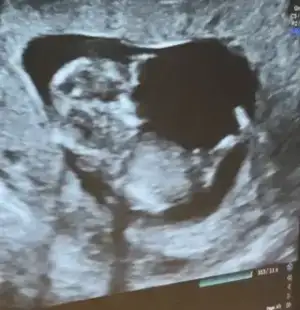

Yani 12 haftalıkken böyleydiUltrason resmin nasıldı senin, son hali![]()

ne bilim anlamadım açıkcası pek bişey :) inşallah gönlündeki olur sağlıklaYani 12 haftalıkken böyleydi![]()